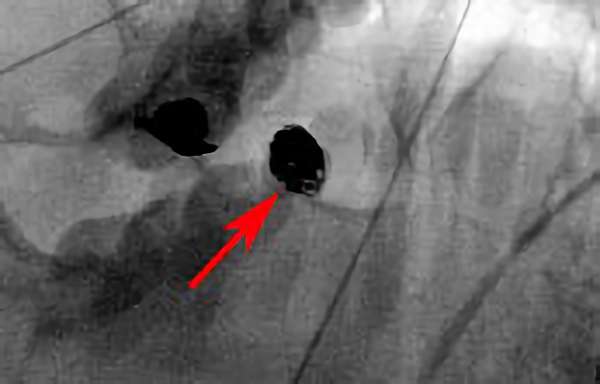

No.1446 手術前

No.1446 手術中

No.1446 手術後

'24年2月

中大脳動脈閉塞症

50代

救急外来